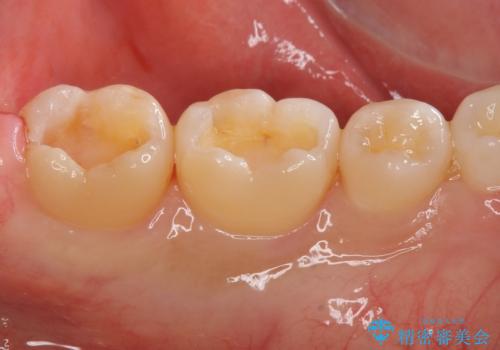

セラミック、ゴールドの詰め物のご案内をしたところゴールドを希望されたのでゴールドインレーで治療を行いました。

ゴールドの詰め物は虫歯の再発のリスクが低い材料になります。